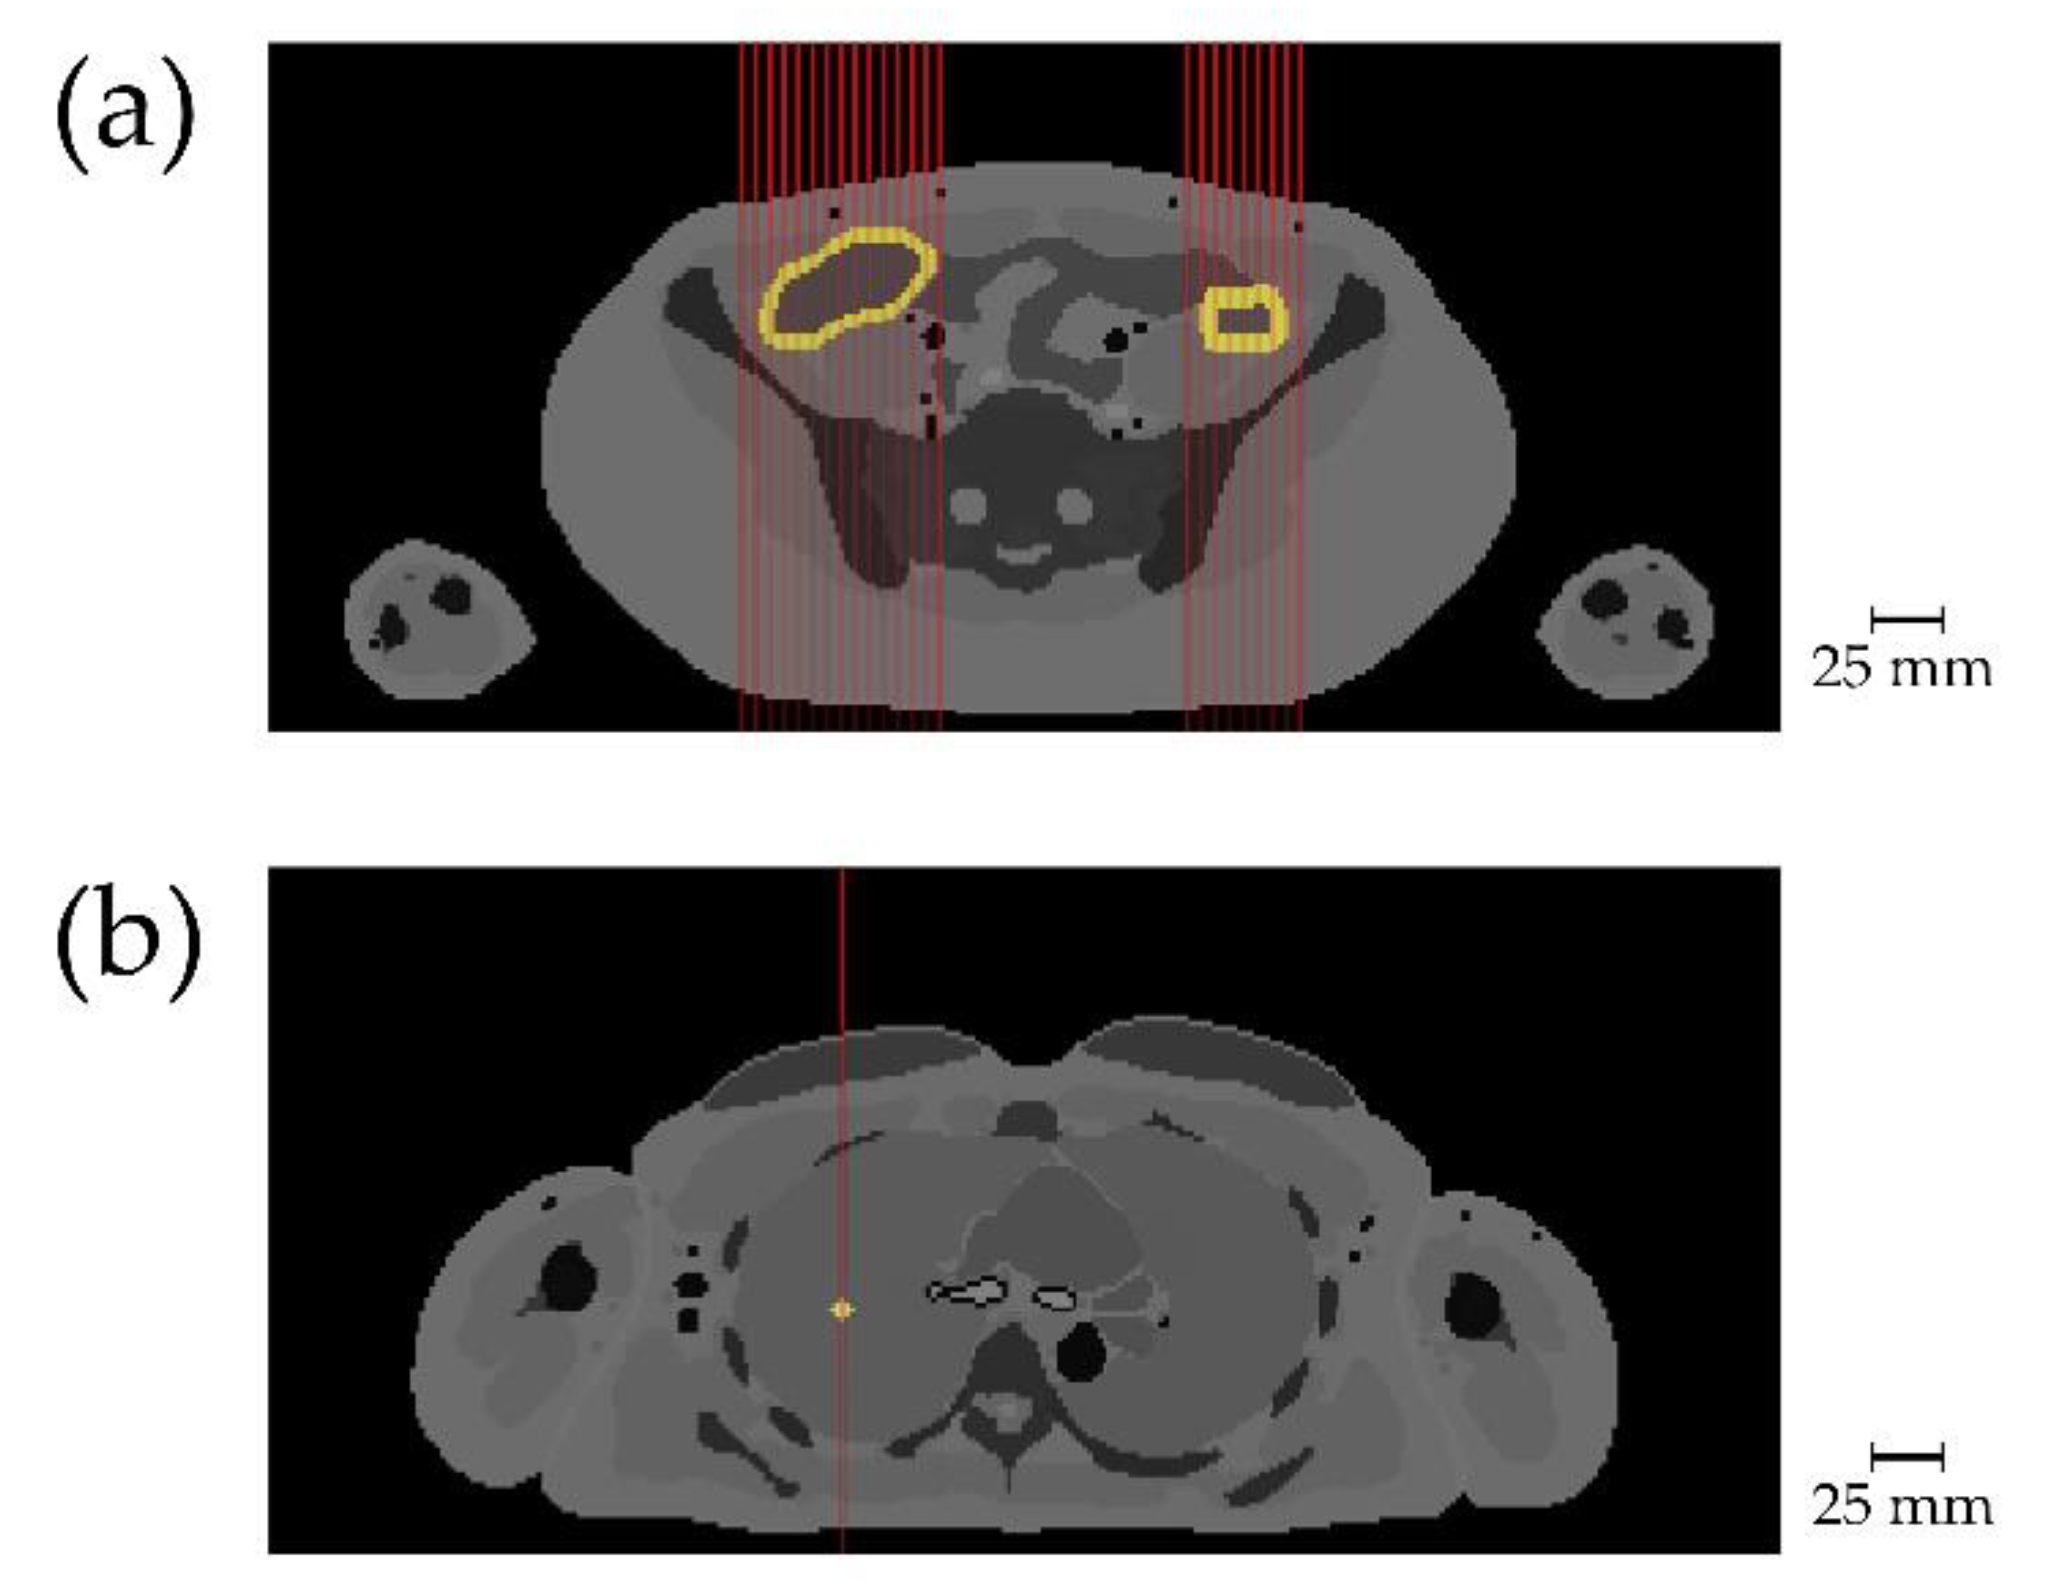

Figure 3.

Scanning positions with target locations. Target tissue with added gold is shown in light yellow, red lines indicate incident X-ray beams. (a) Slice 203 of voxel phantom, entire colon, hence both right and left colon contained gold for scan. Only incident beams for scan from front are shown; (b) slice 277 of voxel phantom with target 4 in right lung. Incident beam shows that here only a single point is scanned. Scale bar in mm, note that one voxel is 1.78 × 1.78 mm wide in this view.